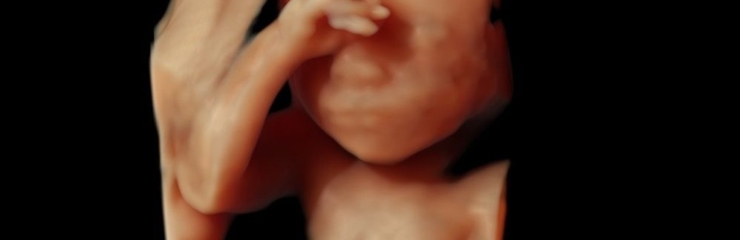

Lootel on juuksed. Ta liigutab oma pead, käsi ja jalgu. Jalad on kätest pikemad. Kui lapsel on tumedate juuste geenid, siis hakkavad need praegu tootma tumedat pigmenti.

Laps teeb rinnaga üksikuid hingamisliigutusi. Väikeaju ja selgroog on moodustunud. Loode on 16 sentimeetri pikkune ja kaalub umbes 130 grammi.

Loote liigutused toimuvad võpatustena. Tal on nii aktiivseid kui ka passiivseid perioode. Pea veresooned on juba nähtavad. Loode saab pead pöörata. Käed ulatuvad kokku.